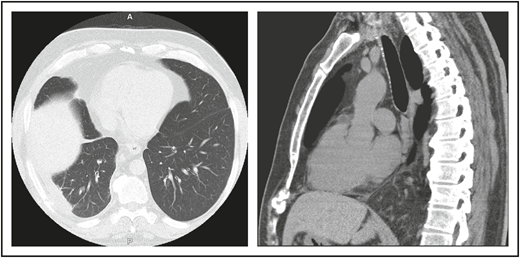

A 46-year-old male contractor who smoked but was previously healthy had acute AIHA. He was treated with prednisone and recovered. This occurred again the following year, and he required blood transfusions. Four years later, AIHA again occurred; he developed a clot in his aorta with thrombosis of his splenic artery, resulting in a splenic infarct. He had a splenectomy and recovered uneventfully. The following year, he developed pneumonia with a large posterior empyema; Streptococcus pneumoniae was cultured (Figure 1). The collection was drained, complicated by a collapsed lung, but he recovered. Six months later, he had a second bacterial pneumonia, and immunoglobulin was measured. These tests showed remarkably low levels of serum immunoglobulins: IgG, 71 mg/dL (normal range, 639-1349); IgA, 6 mg/dL (80-350); and IgM, 15 mg/dL (45-250). He had no protective titers of antibody to any vaccines. Intravenous immunoglobulin replacement was instituted, and the patient experienced no further episodes of either infection or autoimmunity.

(A) The patient in clinical case 1 with several episodes of severe autoimmune hemolytic anemia was only diagnosed with CVID after he had bacterial pneumonia and developed an empyema. (B) Lateral view shows the posterior empyema collection.